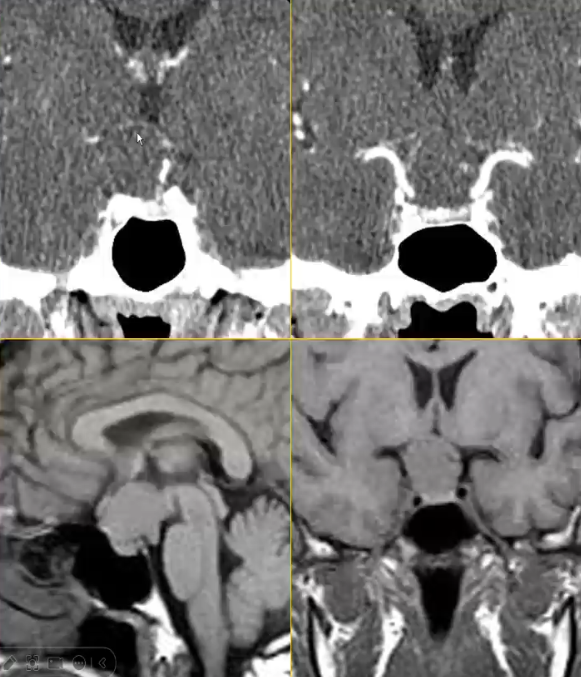

颅咽管瘤

√常发生于鞍上,向鞍内生长,压迫邻近结构

√混杂密度或信号囊实性肿块为其影像学特征,增强后不均匀强化

√50%有钙化